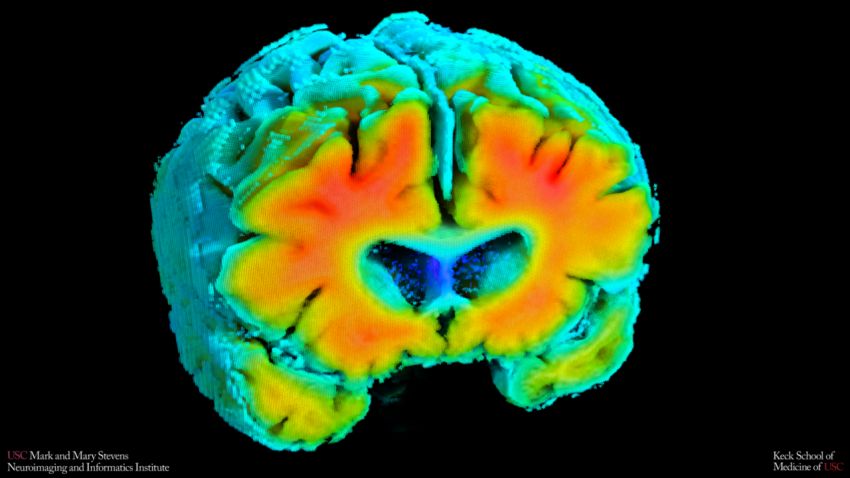

Immagine PET amiloide misura l’accumulo di placche nel cervello. I colori più caldi indicano livelli di amiloide più elevati. (Foto: Stevens INI)

In uno studio pubblicato su Alzheimer's and Dementia, i ricercatori dello Stevens INI hanno scoperto che i valori misurati non invasivamente del flusso sanguigno cerebrale e dell'ossigenazione erano associate a cambiamenti cerebrali caratteristici negli anziani con e senza deterioramento cognitivo, che include l'accumulo di amiloide e un ippocampo più piccolo, una regione essenziale per la memoria. I risultati suggeriscono che la salute vascolare del cervello può avere un ruolo importante nelle prime fasi del processo patologico e potrebbe aiutare a identificare gli individui a rischio prima che compaiano sintomi significativi.

Valori più alti di questi indicatori, quando i vasi sanguigni cerebrali si comportavano più come quelli degli adulti cognitivamente sani, erano collegati a livelli più bassi di placche amiloidi e a un volume dell’ippocampo più grande. Entrambe queste caratteristiche cerebrali sono associate a un minor rischio di MA.